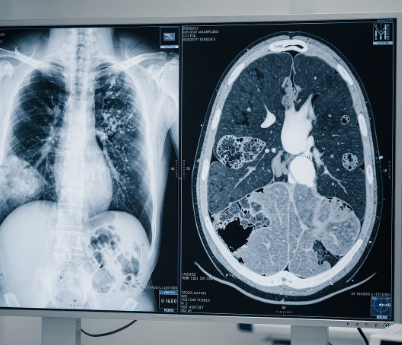

흉부 X선 검사와 객담 검사 진행